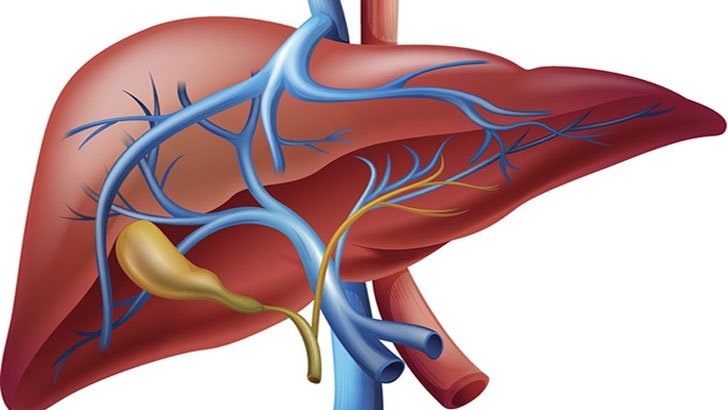

প্রবাস বাংলা ভয়েস ডেস্ক :: ফ্যাটি লিভার বর্তমান সময়ের একটি...